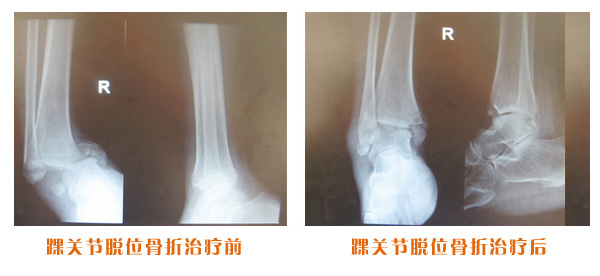

肥城市安駕莊梁氏骨科醫(yī)院是一所以梁氏手法正骨配合膏藥為特色的現(xiàn)代化專科醫(yī)院。

梁氏骨科術(shù)始創(chuàng)于清雍正年間,歷經(jīng)八代,至今已有三百年歷史。據(jù)1929年泰安縣志載“梁瑞圖先生,字增生,號蓮峰,安駕莊人,精岐黃并發(fā)明接骨,凡跌打車凡跌打車軋皮不破而碎骨者......【詳細(xì)】 |